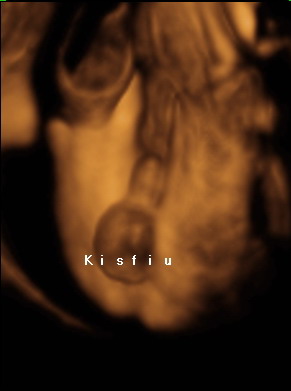

Kislányunk, Emese itt 20+4:

Itt a baba 20 hetes volt, és olyan szépen mosolygott a drága!

Itt a baba 20 hetes volt, és olyan szépen mosolygott a drága!